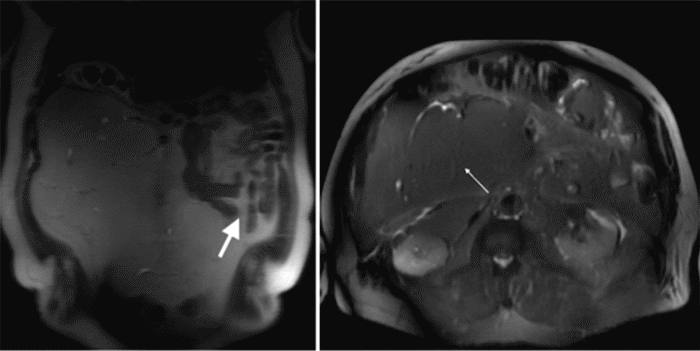

The patient’s postoperative course was complicated by a bile leak requiring percutaneous drainage, atrial fibrillation with rapid ventricular response requiring cardioversion, anasarca, and acute congestive heart failure. Abdominal and pelvic CT demonstrated a large (14.4 × 4.6 × 16.0 cm) heterogenous, fatty-appearing retroperitoneal mass displacing the bowel and abutting the aorta and IVC without obvious invasion of surrounding structures (Figure 2). Due to the concerning size and location of the mass, the patient was referred to our center for further investigation and management.

Figure 2. Subsequent CT Imaging During Management of Postoperative Bile Leak. Published with Permission

Arrows denote internal septations of retroperitoneal mass.

Seven months after the initial presentation, a repeat abdominal and pelvic CT scan revealed significant enlargement of the fatty retroperitoneal mass (20.2 × 28.2 × 14.1 cm) with mass effect on surrounding organs (right kidney, duodenum, colon, liver, inferior vena cava, and pancreas). (Figure 3). Thin internal septations were apparent. Due to rapid tumor growth, significant mass effect, and delays in resection due to post-cholecystectomy complications, the decision was made to proceed with surgical resection without further biopsy. Nine months after initial imaging diagnosis, he was deemed an acceptable surgical risk.

Figure 3. CT Imaging Demonstrates Preoperative Mass Effect. Published with Permission

Small arrow: Denotes the mass significantly impacting adjacent bowel loops. Large arrow: Denotes the mass causing substantial compression of the inferior vena cava

Imaging diagnosis of PLH is challenging due to its similarity to other lipomatous tumors. However, recent case series, after reviewing all reported cases, suggest some findings that may aid in diagnosis. Most PLHs are well-demarcated cystic and solid lesions exhibiting progressive or late enhancement on contrast-enhanced CT or MRI. They are most frequently located in the pancreatic head or uncinate process. MRI can demonstrate the solid component as iso- to low-intensity on T1-weighted images and iso- to high-intensity on T2-weighted images.¹˒³ FDG-PET demonstrates uptake in approximately 20% of patients, potentially leading to misdiagnosis as pancreatic adenocarcinoma.³ Many of these lesions remain stable over time on serial imaging, unlike the rapid growth observed in our patient.³ Our patient’s MRCP revealed multiple irregular nodular soft tissue densities with increased T2WI signal. Contrast-enhanced CT showed multiple internal septae without progressive or late enhancement but did reveal increased vascularity. The large size of our patient’s mass caused significant mass effect on surrounding organs and vascular structures, making it difficult to assess invasion, a feature distinguishing this case from others.